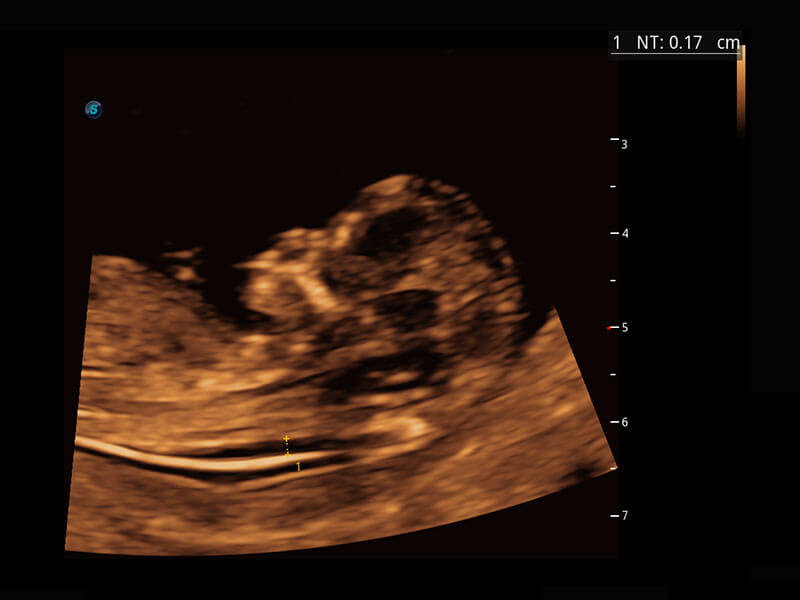

P60在胎儿早孕期超声筛查中为您带来优异的图像质量。

早孕-胎心

高分辨率容积成像-早孕胎儿